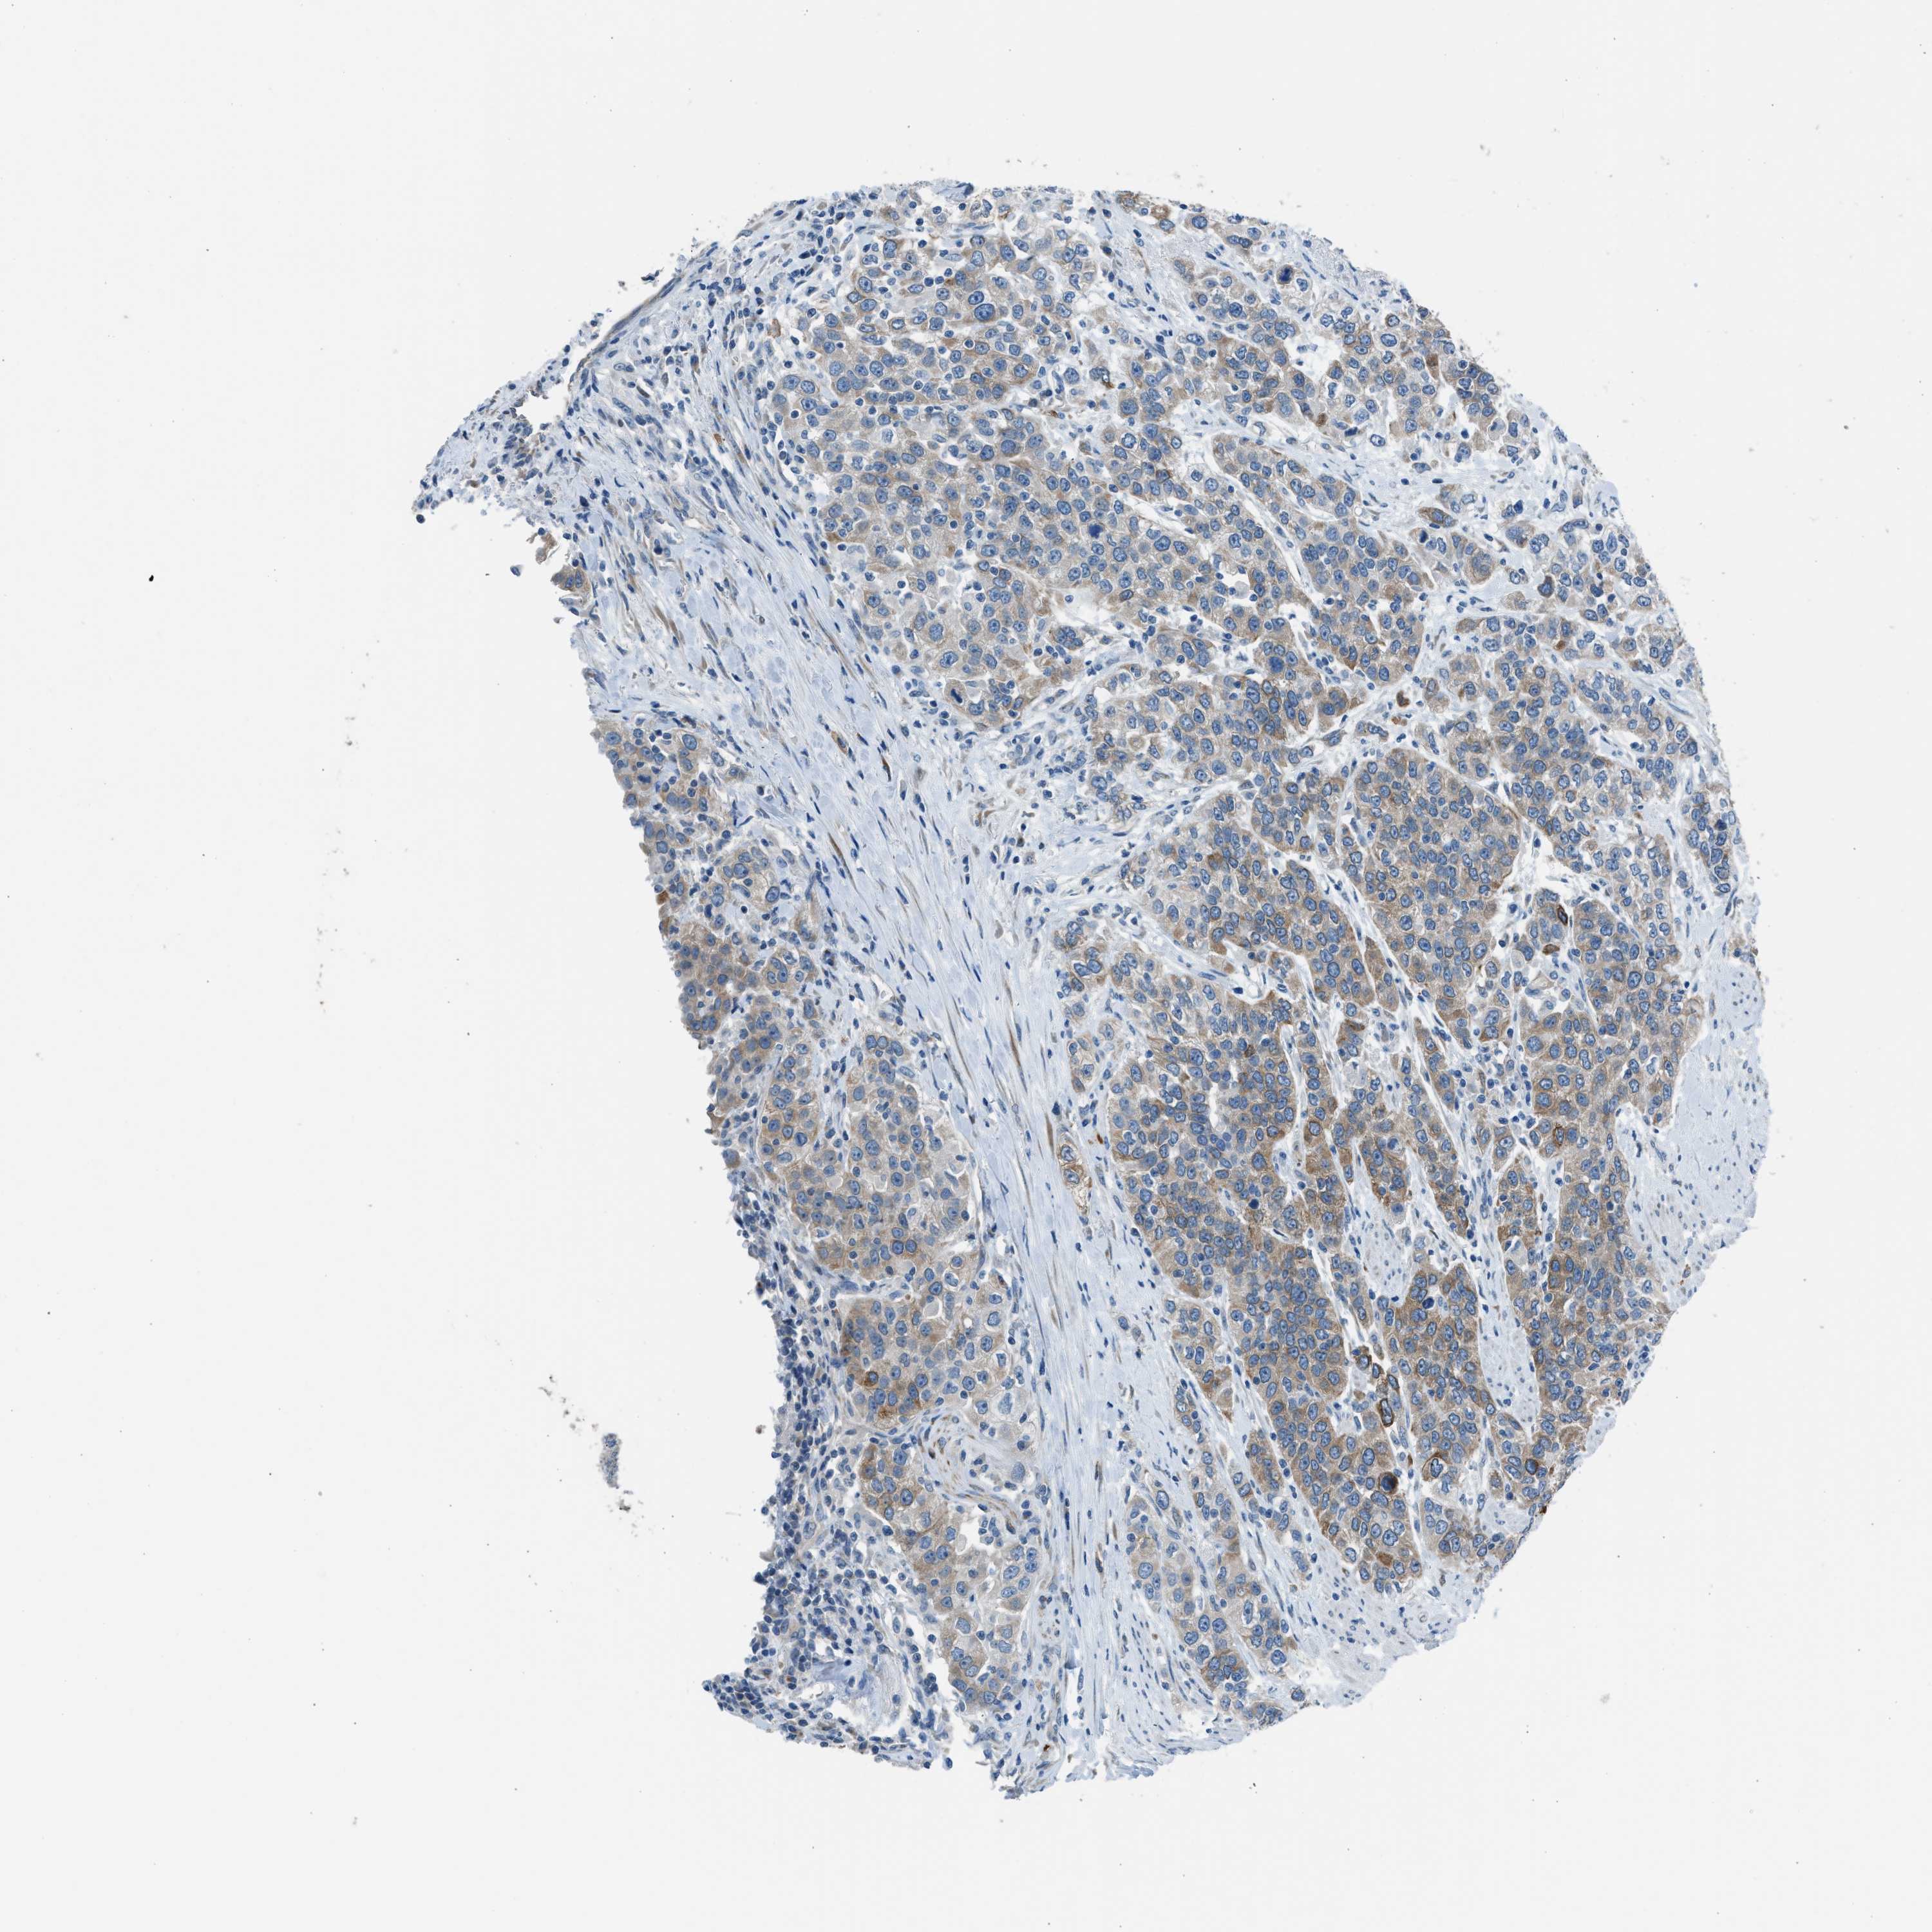

UROTHELIAL CANCER - Protein expressioni

A mouse-over function shows sample information and annotation data. Click on an image to view it in a full screen mode. Samples can be filtered based on level of antibody staining by selecting one or several of the following categories: high, medium, low and not detected. The assay and annotation is described here.

Note that samples used for immunohistochemistry by the Human Protein Atlas do not correspond to samples in the TCGA dataset.

Antibody stainingi

Antibody staining in the annotated cell types in the current human tissue is reported as not detected, low, medium, or high, based on conventional immunohistochemistry profiling in selected tissues. This score is based on the combination of the staining intensity and fraction of stained cells.

Each image is clickable and will lead to virtual microscopy that enables deeper exploration of all samples and also displays staining intensity scores, fraction scores and subcellular localization as well as patient and tissue information for each sample.

Antibody HPA016812

Staining

High

Medium

Low

Not detected

Intensity

Strong

Moderate

Weak

Negative

Quantity

>75%

75%-25%

<25%

None

Location

Nuclear

Cytoplasmic/membranous

Cytoplasmic/membranous,nuclear

Urothelial carcinoma, Low grade

Urothelial carcinoma, High grade